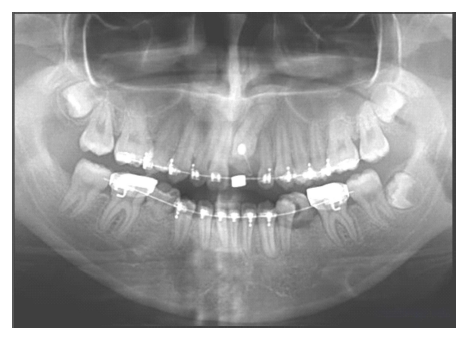

Female, 15 years old. As with Case 1, the inferior left canine was the only primary tooth remaining in the mouth (Fig. 3). The radiograph showed that the 3.3 exhibited a type 2 transmigration (Figs. 4, A and B). The tooth was located closer to the mandible edge than in Case 1, precluding the use of orthodontic traction, and it was decided to monitor the tooth. Dental protrusion was the initial reason for the appointment, and the patient requested orthodontic treatment of this condition. Because the 3.3 was far from the roots of the neighboring teeth, the orthodontist decided there would be no risk in moving teeth in this zone. To correct the protrusion, the first premolars were extracted (except for quadrant 3 since the 3.3 was transmigrated). The 3.3 would not be restored in this treatment since the 3.4 would take its place. The 1-year follow-up panoramic x-ray showed no significant changes (Fig. 4C).

Female, 18 years of age. The inferior right primary canine was still present (Fig. 5). Radiography showed that the 4.3 was in type 2 transmigration and showed the presence of at least three supernumerary teeth near the 4.3 (Fig. 6, A and B). The patient was referred to a maxillofacial surgeon to evaluate the possibility of surgical extraction, but the proximity of the 4.3 to the mandible edge made this possibility untenable. As in Case 2, the space between the transmigrated tooth and its neighbors allowed for orthodontic manipulation. The option of opening a space and rehabilitating the transmigrated canine was offered to the patient, who accepted. The 2-year follow-up panoramic x-ray showed no significant changes (Fig. 6C).

Male, 12 years of age. During clinical examination in preparation for orthodontic treatment, the inferior right primary canine was found to be present (Fig. 9). The radiograph showed the 4.3 to be in type 2 transmigration and that a supernumerary tooth was reabsorbing the root of the previously- mentioned primary canine (Fig. 10A). After the treatment options were explained, the patient decided for surgical removal of the 4.3. A restorative dentist found that the supernumerary tooth had a crown and root sufficiently large to be used in a fixed prosthesis. It could therefore be maintained and treated with prosthetics instead of using a dental implant or bridge. The primary 4.3 was extracted and a space opened for future restoration using orthodontics (Fig. 10B).

Male, 22 years of age. This patient was missing various teeth. He requested a treatment evaluation during which the 1.3, 3.3, and 3.6 were found to be absent (Fig. 11). The patient indicated that the 3.6 had been extracted due to dental caries. The radiograph showed that the 1.3 was impacted and that the 3.3 was in type 1 transmigration. In addition, the 2.2 exhibited root resorption of half the root. The distal face was more severe, suggesting that during eruption the 2.3 had damaged the adjacent root (Fig. 12A). Due to the proximity of the 3.3 to the incisor roots, it was suggested that it be removed, to which the patient agreed (Fig. 12B). Orthodontic treatment of the 1.3 was initiated to later surgically expose it and move it into the dental arch.

Female, 16 years of age. The 1.5, 2.1, 3.5, 4.3, and 4.5 teeth were missing, and the inferior right primary canine and two primary second molars were still present (Fig. 13). The radiograph showed that the 4.3 was in type 1 transmigration, the 1.5, 3.5, and 4.5 exhibited agenesis, and the 2.1 was impacted and had an associated supernumerary tooth (Fig. 14A). The simultaneous presence of supernumeraries and agenesis is a very rare (0.33%) condition known as concomitant hypo-hyperdontia (14). As in Case 6, the 4.3 was near the roots of neighboring teeth and the CBCT revealed a lesion that extended from the right deciduous canine to the left lateral incisor, almost as if showing the path that the transmigrated canine had followed (Fig. 14, B-D), so it was extracted. The 2.1 was surgically exposed and a post attached to it to allow its movement with orthodontics. The gap for the 1.5 was to be closed using orthodontics, but the spaces for the inferior premolars were to be maintained for later rehabilitation with dental implants (Fig. 15).